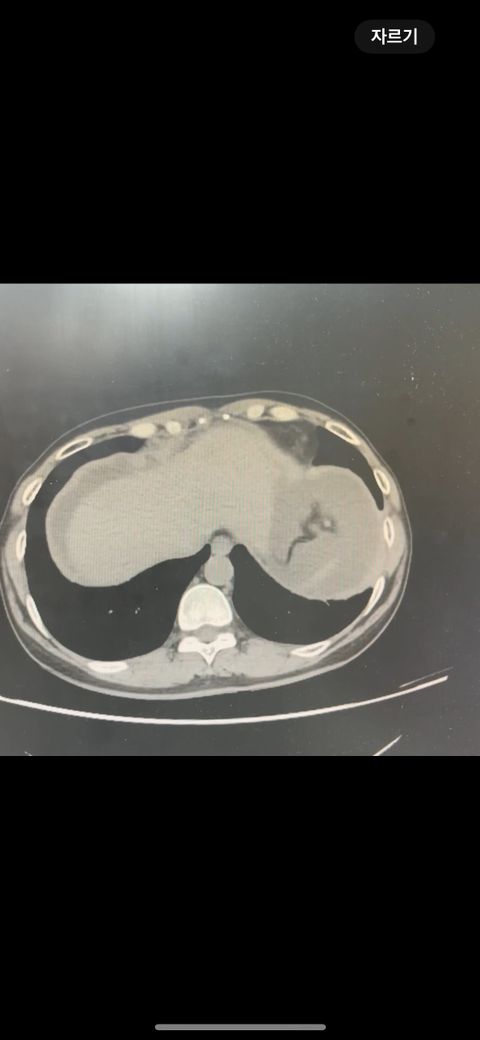

복부 ct (contrast) 영상 판독해주세요!!

어제 복부 ct 촬영하였는데 판독 하려면 시간이 걸려서 미리 알 수 있을까요? 지금 증상은 윗배가 많이 나왔고 허리 아프고 조금만 밥 먹어도 배부른 상태입니다..

어제 말씀드린대로 자궁 쪽에 불규칙한 음영들이 보이고 있어 물혹이 있는 것으로 의심해 볼 수 있으며, 이외에 복부에 가스가 조금 차있거나 비장이 약간 커져 있는 듯한 모습이 보이나 일부 단면만으로 유추한 것이라 판독 상 틀릴 가능성도 있겠습니다.